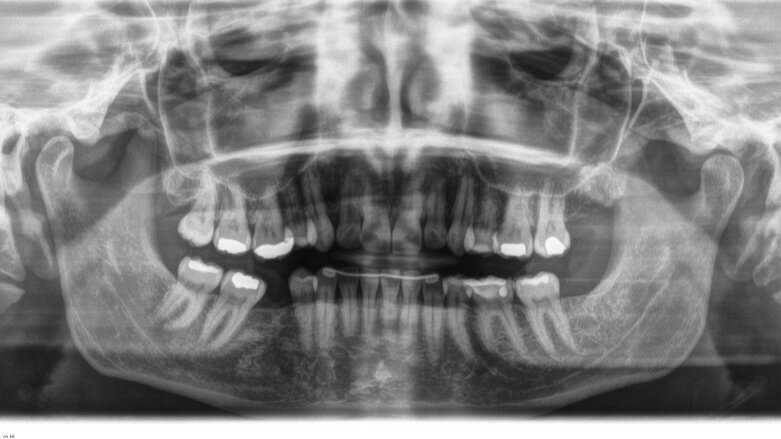

L’esame ortopantomografico (Fig. 3) non ha evidenziato patologie in atto e confermava l’aumentato tipping del secondo e del terzo molare inferiori di destra. La paziente non riferiva alcun disturbo a carico delle articolazioni temporomandibolari. Nella pianificazione del trattamento la paziente è stata informata della presenza di una malocclusione di seconda classe monolaterale per la quale è stata proposta una risoluzione mediante distalizzazione dell’emiarcata superiore di sinistra e uprighting degli elementi 4.7 e 4.8. È stata inoltre informata che la sovraeruzione dell’elemento 1.6 non consentiva di riabilitare l’edentulia in maniera ottimale. La durata del trattamento ortodontico proposto era stimata in 18- 24 mesi. La paziente ha preferito non procedere con un trattamento ortodontico onnicomprensivo, ma ha accettato la proposta alternativa di un trattamento breve con allineatori trasparenti al fine di effettuare l’intrusione dell’elemento 1.6 per ottimizzare la terapia implantoprotesica. Sono stati utilizzati allineatori in poliuretano caratterizzati da una linea di taglio non festonata, ma dritta passante circa 2 mm apicale ai margini gengivali degli elementi dentari (ClearCorrect, Round Rock, Texas, USA).

Fig. 3 - Ortopantomografia pre-trattamento.